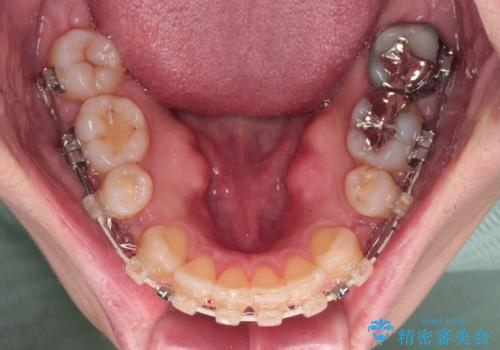

- 口元の突出感と下の前歯のがたつきを主訴として来院された患者様です。

口元の突出感と叢生改善のため上下左右の第一小臼歯4本を抜歯し、ワイヤー装置にて矯正治療を行うこととしました。

なるべく目立たない装置が希望だったため、審美装置で治療を行いました。

左上はアンカースクリューを併用することでスムーズに抜歯スペースを閉じることができました。